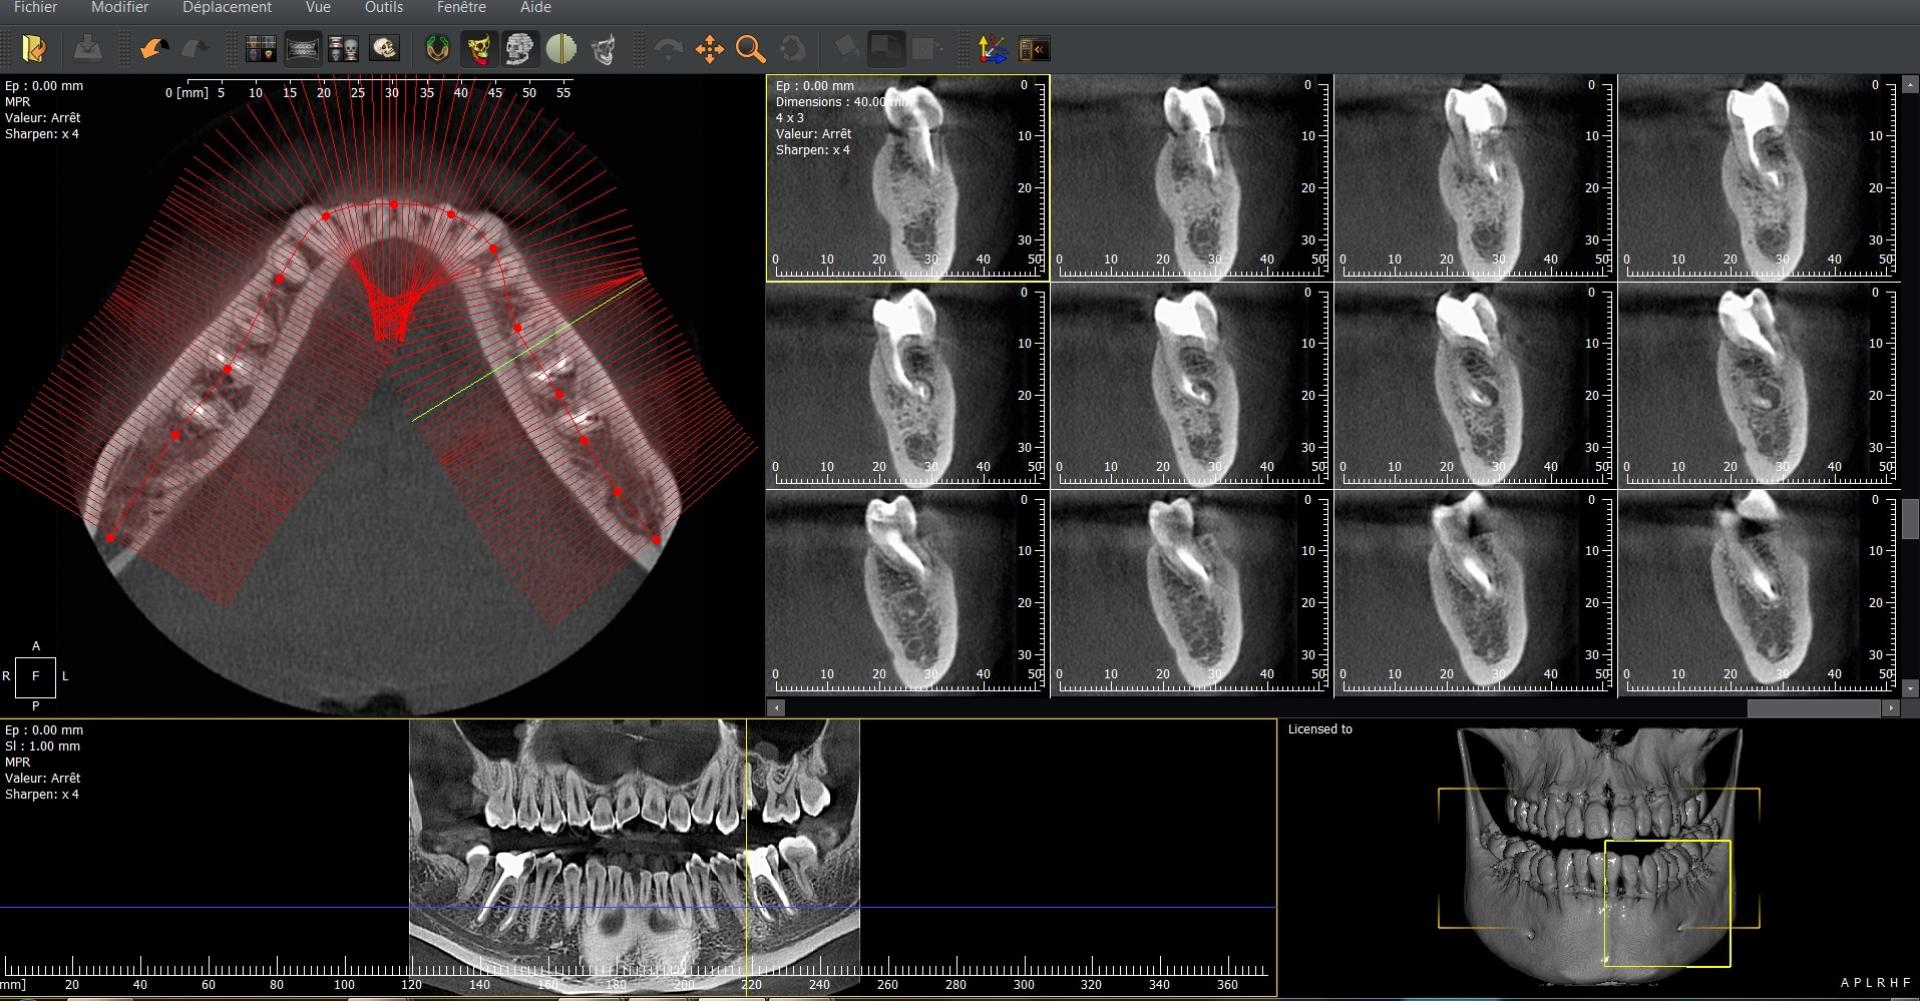

La radiographie volumique par faisceau conique (CBCT) représente une évolution majeure dans le domaine de l’imagerie médicale et dentaire. Cette technologie fournit des images tridimensionnelles précises des structures anatomiques, essentielles pour la planification préopératoire et les diagnostics complexes. Le code LAQK027 a été spécifiquement attribué à cet acte afin d’en standardiser la pratique et la facturation au sein de la nomenclature médicale.

Le Cone Beam Computerized Tomography (CBCT) se distingue de la radiographie classique en offrant une vision volumétrique complète. Grâce à un faisceau de rayons X conique qui tourne autour du patient, des centaines d’images sont capturées en quelques secondes, puis reconstruites numériquement pour former un modèle 3D détaillé. Cette approche permet une analyse fine des tissus durs, notamment des dents et des structures osseuses.

La radiologie volumique par faisceau conique (CBCT), également appelée Cone Beam, est aujourd’hui un outil incontournable dans de nombreux domaines médicaux et dentaires. Grâce à sa précision tridimensionnelle et à sa faible dose de rayonnement, elle permet une analyse détaillée des structures osseuses et dentaires, offrant aux praticiens une vision complète pour le diagnostic et la planification thérapeutique.

En implantologie, elle facilite la planification préopératoire en fournissant une représentation fidèle de la densité et du volume osseux, réduisant considérablement les risques de complications chirurgicales.